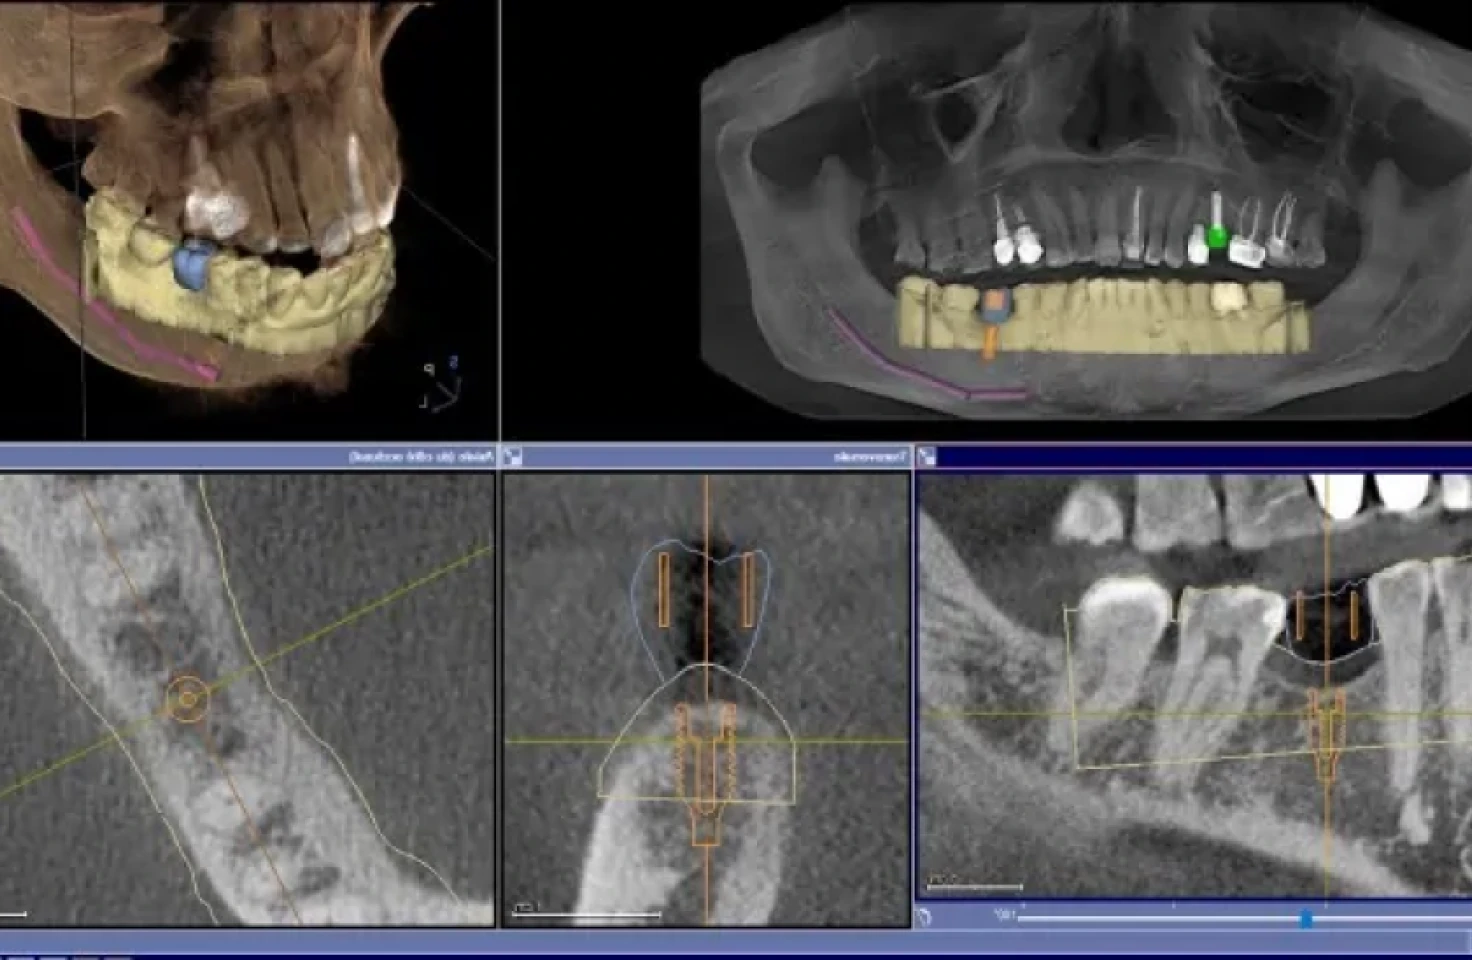

Radio panoramique 3D au cabinet du Dr Mathieu Benichou à Toulouse

La radiographie panoramique et 3D permet au praticien un expertise affinée et précise des tissus dentaires et maxillaires.

Permettant de diagnostiquer des pathologies de manière plus précise, permet une planification rigoureuse des chirurgiens reconstructrices et implantaires .